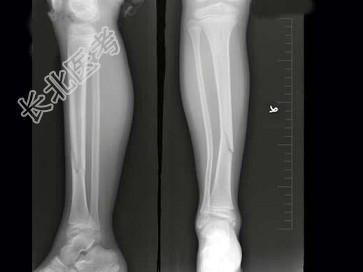

- 单项选择题女,8岁, 外伤后致右胫骨骨折,如图所示, 下列描述正确的是 ( )

A、对位好,对线差

B、对位差,对线好

C、对位对线好

D、对位对线差

E、以上均不正确